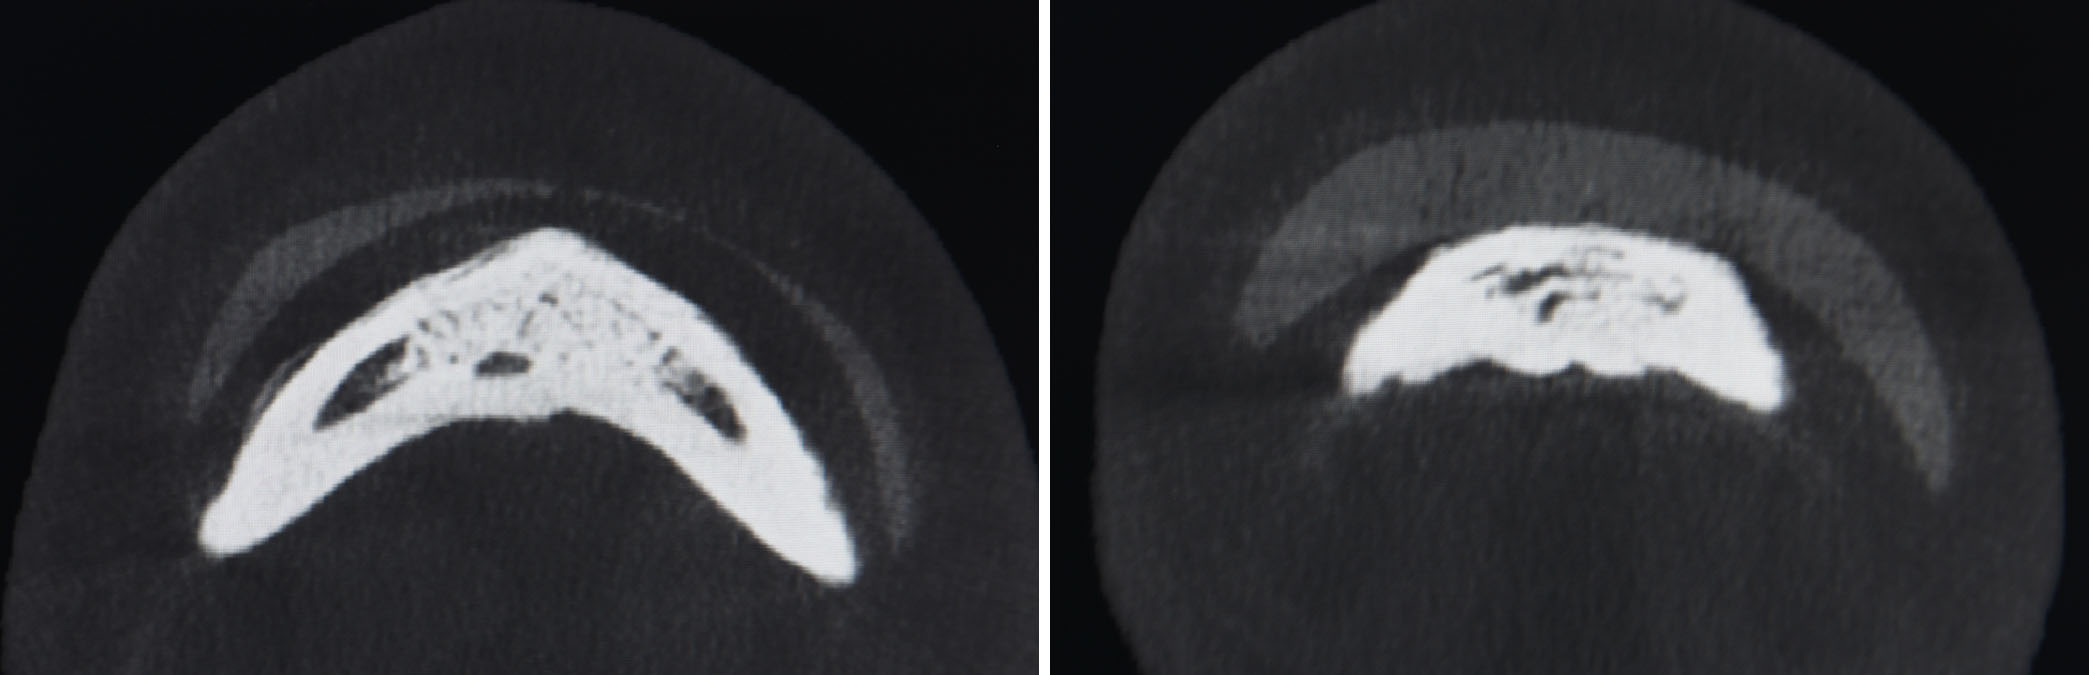

Non-Fitting Anatomic Chin Implant in a Female CT scan Dr Barry Eppley Indianapolis